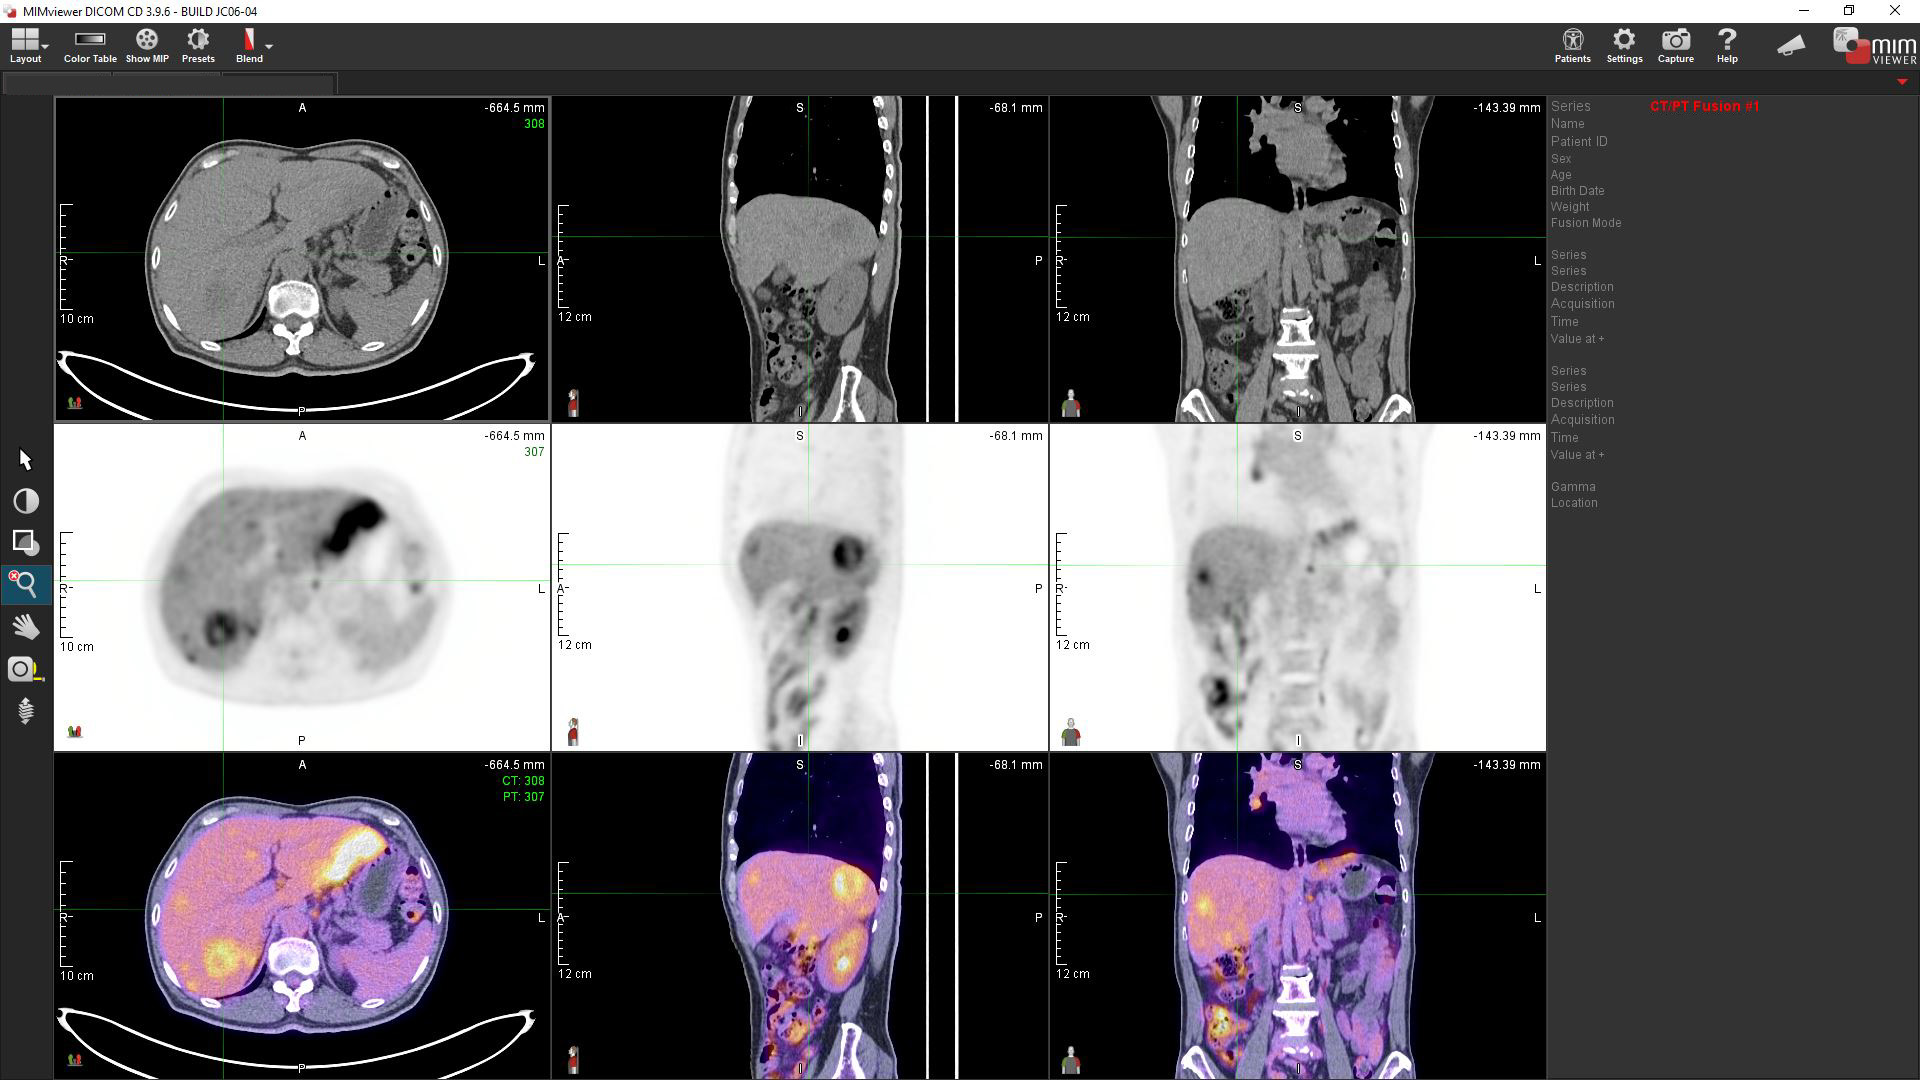

Adopting close to 20 types of PET radiopharmaceuticals specified to different types of cancer cells based on biochemical metabolism or receptor density at molecular level is the unique feature of PET/CT scan in HKSH. PET/CT “fusion image” combines data from the two imaging modalities, with PET providing cellular functional information while CT applies attenuation correction for quantification of PET data on tumour pathophysiology. The presence of iodinated CT contrast media will affect accuracy of PET quantitative data (such as SUV) during interpretation of images. Moreover, kidney function may also be hindered by contrast media. Iodine content in contrast media may induce allergic reaction. Patient will also receive more than double amount of unnecessary radiation dosage, if an extra wholebody contrast CT scan comes along with the plain PET/CT scan.

A color-printed booklet with a Write-Once USB drive will be provided as a standard package. All the scan data and relevant pathology images captured by nuclear medicine specialist are included. Using the MIM Viewer software provided, referral doctors or patients can view the images with their own computer. You can also request our staff to upload your images and reports to the Electronic Health Record Sharing System (eHRSS) run by the HKSAR Government to facilitate information sharing among participating hospitals and clinics including the Hospital Authority.